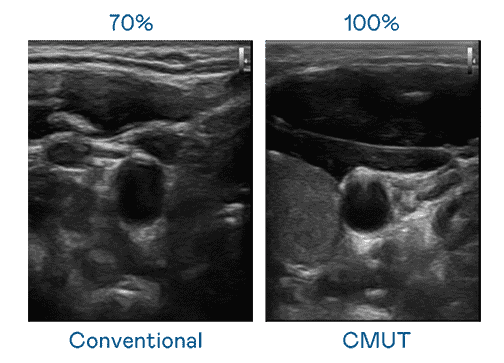

CMUT 技术是一种用电容式微机电元件来产生超音波讯号的技术。。与传统 PZT 压电式技术相比,,CMUT 频宽增加 30%,,更宽频的超音波讯号让影像解析度大幅提升,,,,是实现高影像品质医疗超音波扫描、、、促进精准医疗发展的关键技术。。

大频宽带来超清晰影像

超音波影像的解析度高低,,,,首先取决于探头能发出的讯号频宽。。。龙门国际 CMUT 可提供高清晰的超音波讯号,,,,提供高频宽、、高灵敏度、、影像纹理细节更高的超音波影像,,,协助医护人员缩短影像判读时间及利用精准的医疗影像进行诊断。。。。